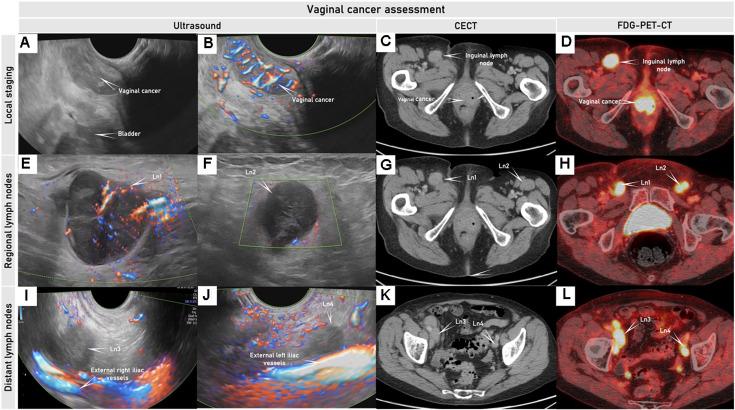

妇科癌症的影像学分期和超声的作用:欧洲联合共识声明的更新。

Staging by imaging in gynecologic cancer and the role of ultrasound: an update of European joint consensus statements.

In recent years the role of diagnostic imaging by pelvic ultrasound in the diagnosis and staging of gynecological cancers has been growing exponentially. Evidence from recent prospective multicenter studies has demonstrated high accuracy for pre-operative locoregional ultrasound staging in gynecological cancers. Therefore, in many leading gynecologic oncology units, ultrasound is implemented next to pelvic MRI as the first-line imaging modality for gynecological cancer. The work herein is a consensus statement on the role of pre-operative imaging by ultrasound and other imaging modalities in gynecological cancer, following European Society guidelines.

摘要

近年来,盆腔超声诊断成像在妇科癌症的诊断和分期中的作用呈指数级增长。来自最近的前瞻性多中心研究的证据表明,术前局部超声分期在妇科癌症中具有很高的准确性。因此,在许多领先的妇科肿瘤学单位,超声与盆腔 MRI 一起被用作妇科癌症的一线成像方式。本文是根据欧洲社会指南,就超声和其他成像方式在妇科癌症中的术前成像作用达成的共识声明。